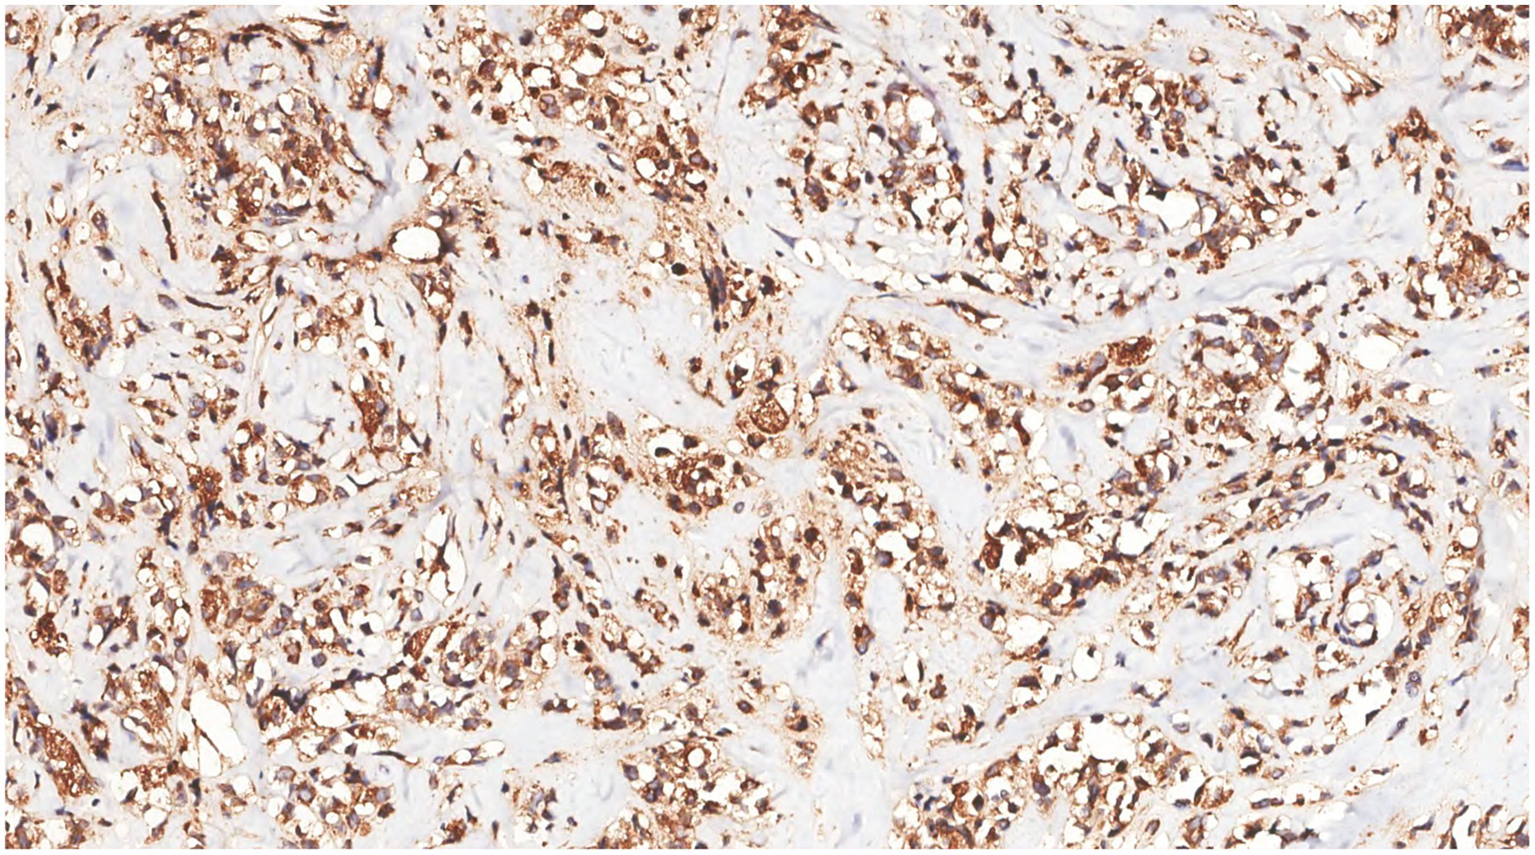

Immunohistochemical analysis of tumor cells revealed the following: Vimentin (+), LCA (+) (Figure 9), MPO (+) (Figure 10), CD68 (+) (Figure 11), CD117 (+) (Figure 12), CD15 (+) and CD123 (in +), CD34 (in +), CK (−), CD20 (−), CD3 (−), GATA3 (−), TRPS1 (−), and Ki-67 (70%+).

Figure 10

Immunohistochemistry showed MPO(+) in tumor cells.

Figure 12

Immunohistochemistry showed that the tumor cells were CD117(+).